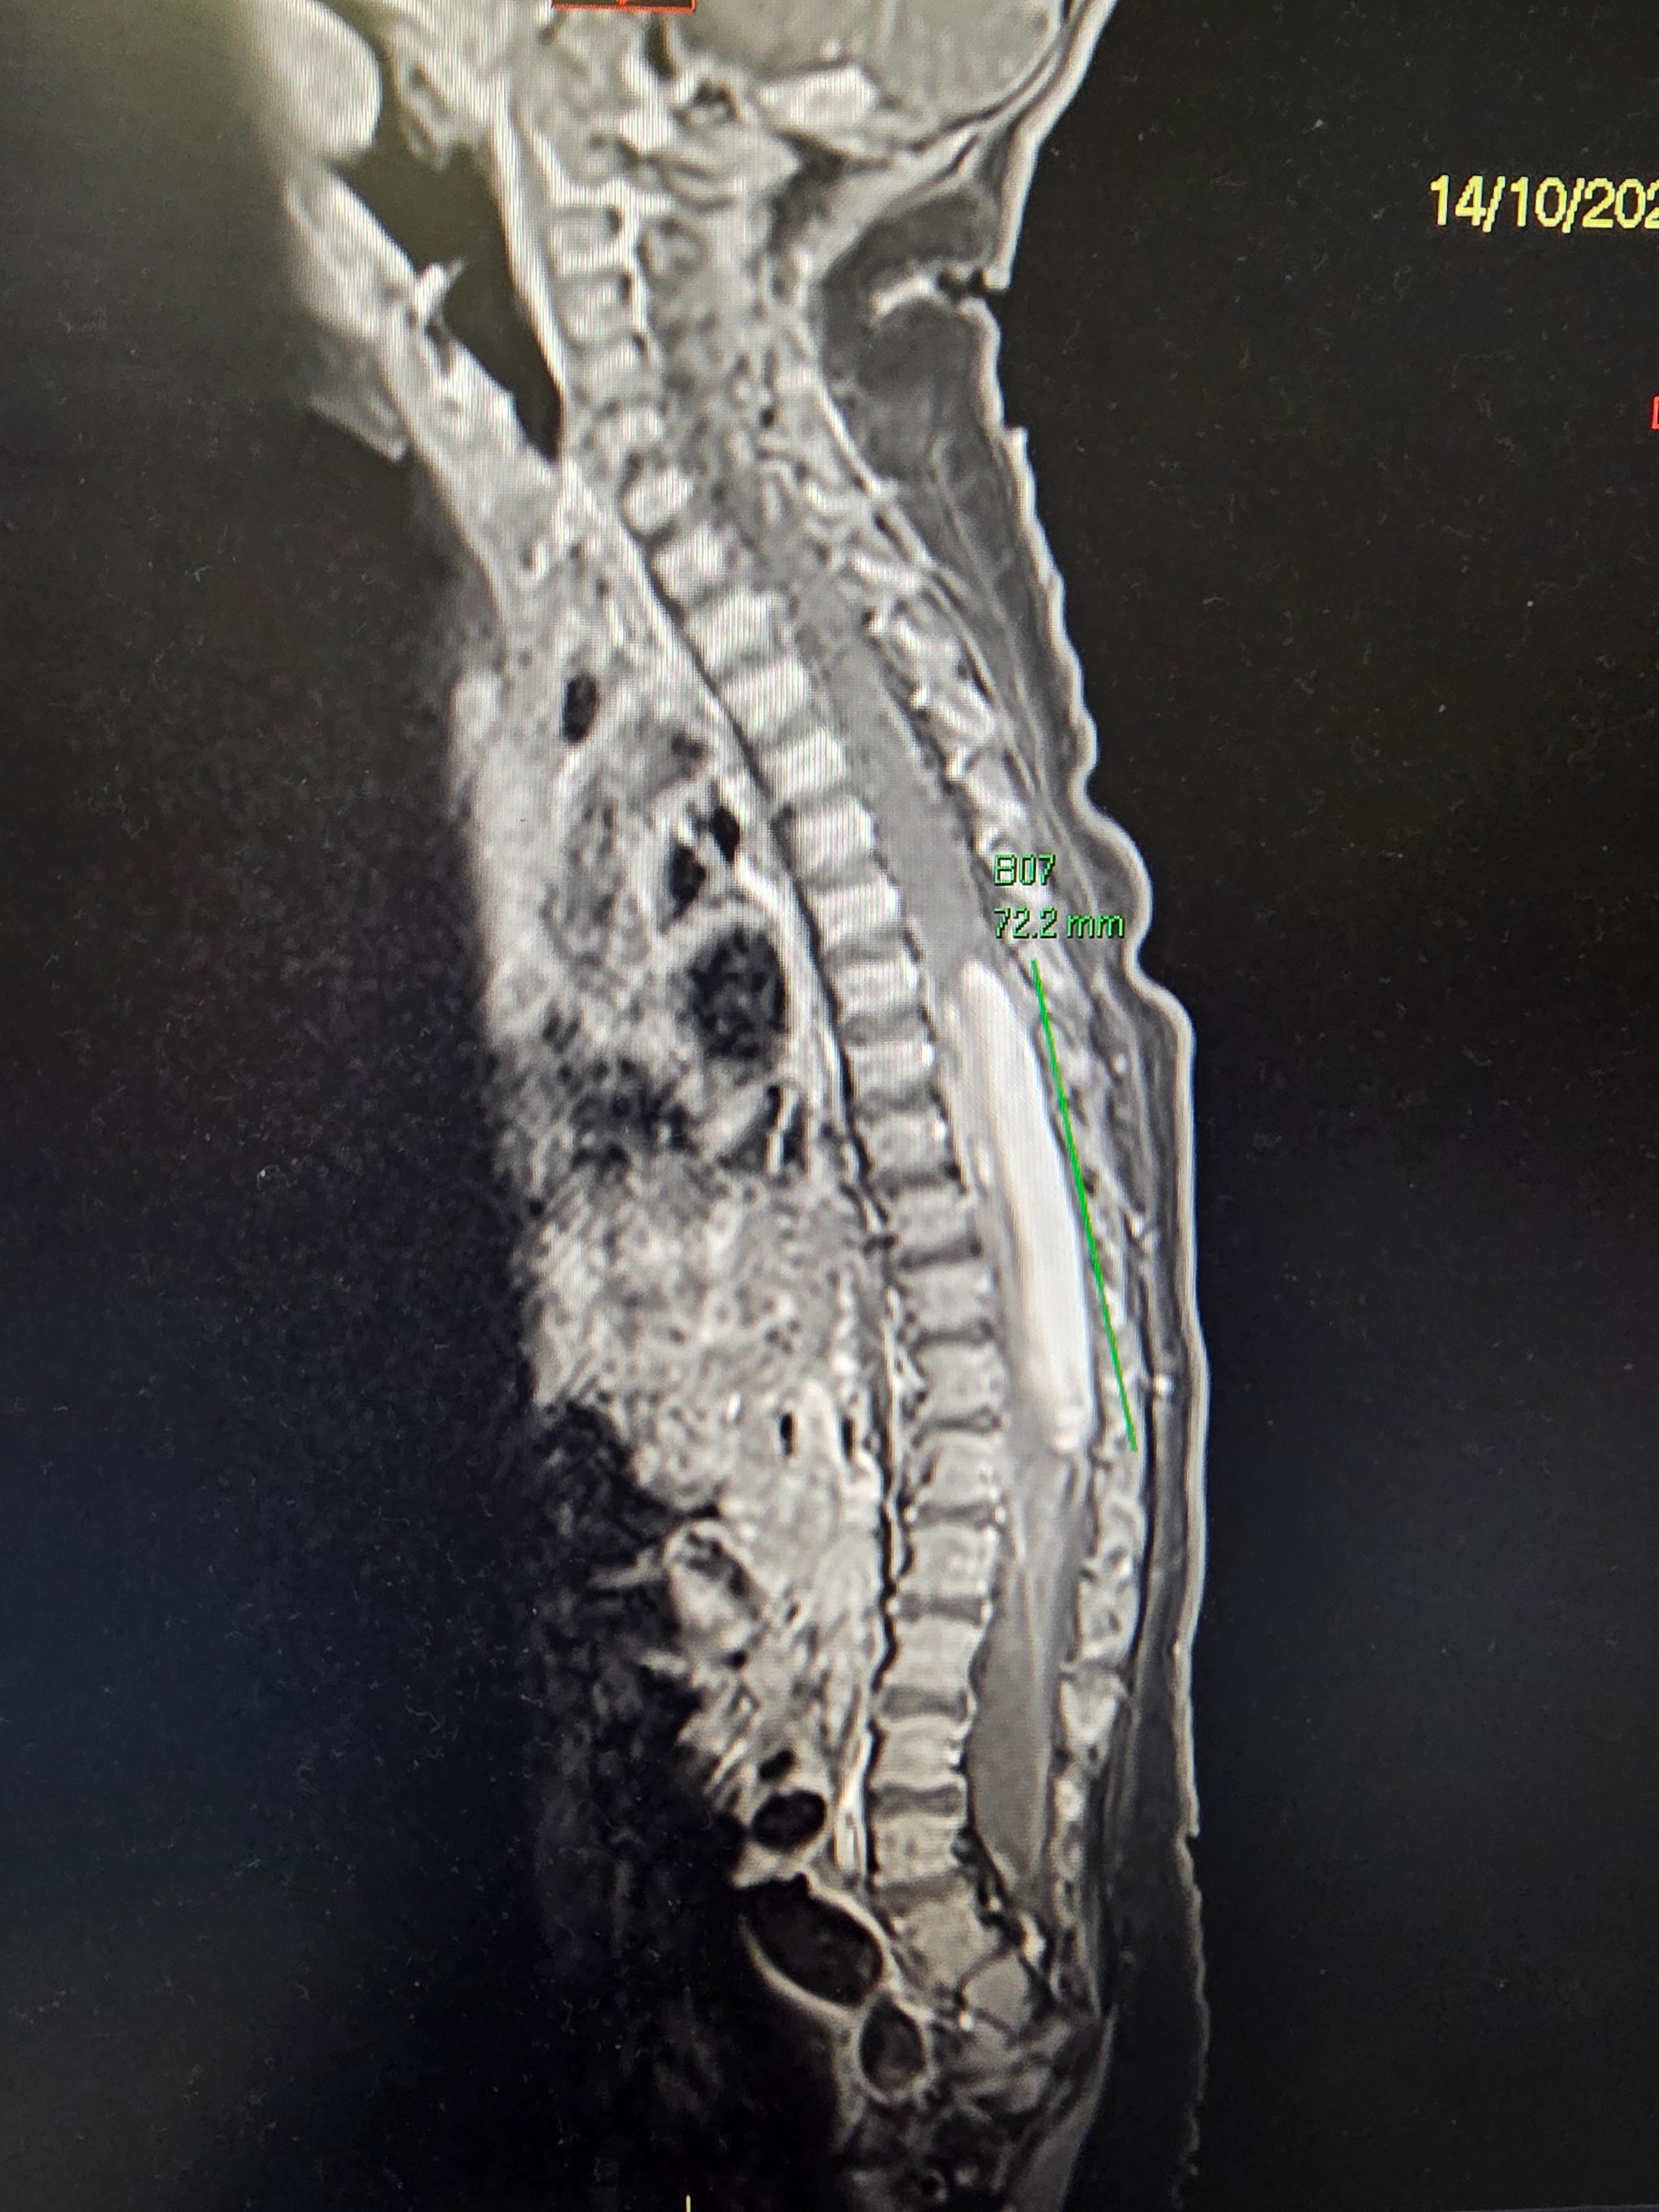

That’s when our world stopped. They told us Jaxson had a 10 cm tumour on his spine — the reason he’d lost the use of his left leg and his body was twisting to one side. They said that if they didn’t operate within days, he would be paralysed.

The next few days were rough. They had to cut through seven vertebrae, leaving an incision that stretched from the middle of his shoulders to his waistline. He was on strict flat-bed rest. But the surgeons did an incredible job — they removed about 75 % of the tumour while preserving neurological function. The rest was too deeply intertwined with his spinal nerves to ever remove.

After ten long days, we finally convinced them to do another MRI — which happened to fall on his first birthday.

Halfway through the small hospital-garden birthday party we’d planned for him and his older brother, we were told to come immediately for his scan. We sat outside recovery waiting to see him when a doctor approached and asked if the neurosurgery team had spoken to us yet. We said no. That’s when she told us the news that shattered us completely: the tumour had regrown, larger than before — in just two weeks.